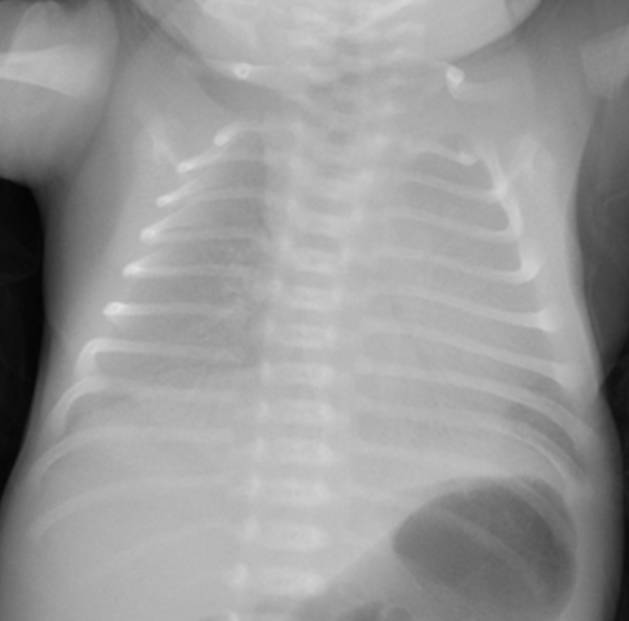

典型胸片結果:

(白肺表現(xiàn),IV級肺透明膜病變)